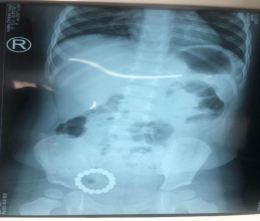

一周前,2歲的童童在家玩耍套在手腕上五顏六色的磁力手串,感到非常稀奇,當作「糖豆」吃進了肚,家長發現後觀察3天也沒有在糞便中發現磁力珠排出體外,於是緊急帶孩子來到哈爾濱市兒童醫院普外二科就診。劉冰洋醫師接診患兒後完善相關檢查,經腹部拍片和腹部超聲檢查顯示小腸有多枚金屬異物,其中跨越腸壁,腫脹明顯,考慮已造成局部腸壁穿孔。

張浩然主任評估患兒已存在腸內瘺可能,考慮減少患兒創傷,選擇經腹腔鏡下行消化道內異物取出術。術中見磁力珠位於迴腸腸腔內,磁性吸附造成兩段腸壁局部粘連伴擴張,分離後見粘連處存在腸壁穿孔,通過腹腔鏡彎鉗取出16枚磁珠後,並進行了破損腸壁修補。